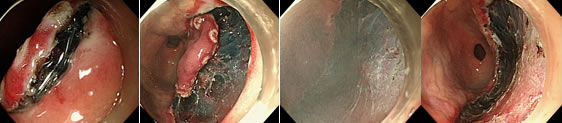

내시경 시행 중 용종이 발견되었을 경우 작은 용종은 겸자를 이용해서 단순 제거를 하게되고, 5mm 이상의 용종은 크기에 따라 점막 절제술 (Endoscopic Mucosal Resection, EMR) 혹은 용종 절제술 (Hot Snare Resection)을 시행하게 됩니다. 점막하층에 용액을 주입하여 병변을 융기시킨 후 올가미(snare) 등을 이용하여 절제술을 시행하게 됩니다.

상부 내시경, 대장 내시경에서 2cm 이상의 큰 병변이나, 종양성 병변이 발견될 때에는 내시경적 점막하 박리절제술 (Endoscopic Submucosal Dissection, ESD)을 시행할 수 있습니다. 본원에서는 위장, 대장의 점막하 박리절제술이 모두 가능합니다.

위장관 출혈시 출혈원인을 진단하고 출혈 원인에 대한 다양한 내시경적 지혈술을 시행하는 것을 말합니다. 약물의 주사요법부터 지혈클립술, 전기를 이용한 응고요법, 그리고 고무밴드 결찰술 등을 시행할 수 있으며 이 시술의 도입으로 궤양출혈시 외과적인 수술을 시행하는 경우는 점점 드물어지고 있으며 시술에 대한 지혈 성적은 매우 우수합니다.

강견변증 환자의 식도 정맥류의 출혈은 단시간에 많은 혈액이 빠져나가기 때문에 출혈 이후 최대한 빠른 시간 내에 치료를 해야 합니다. 내시경을 이용하여 식도내강내로 튀어나온 식도정맥류를 고무밴드로 묶어서 더 이상 출혈을 못하게 할 뿐 아니라 식도 정맥류 자체를 제거할 수 있습니다.